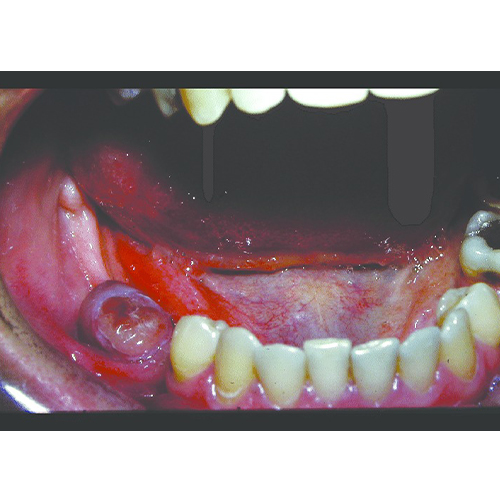

۱) پیوژنیک گرانولوما: یک ضایعه برجسته روی لثه است ( البته گاهی روی زبان و سایر مخاط هم دیده میشود) با کوچکترین دستکاری خونریزی میکند و اندازه آن شاید به چندین سانتی متر هم برسد. دلیل بروز آن شاید جرم زیر لثه باشد و شاید تغییرات هورمونی در زنان به ویژه در ایام بارداری.

تصاویری از تومورهای دهانی